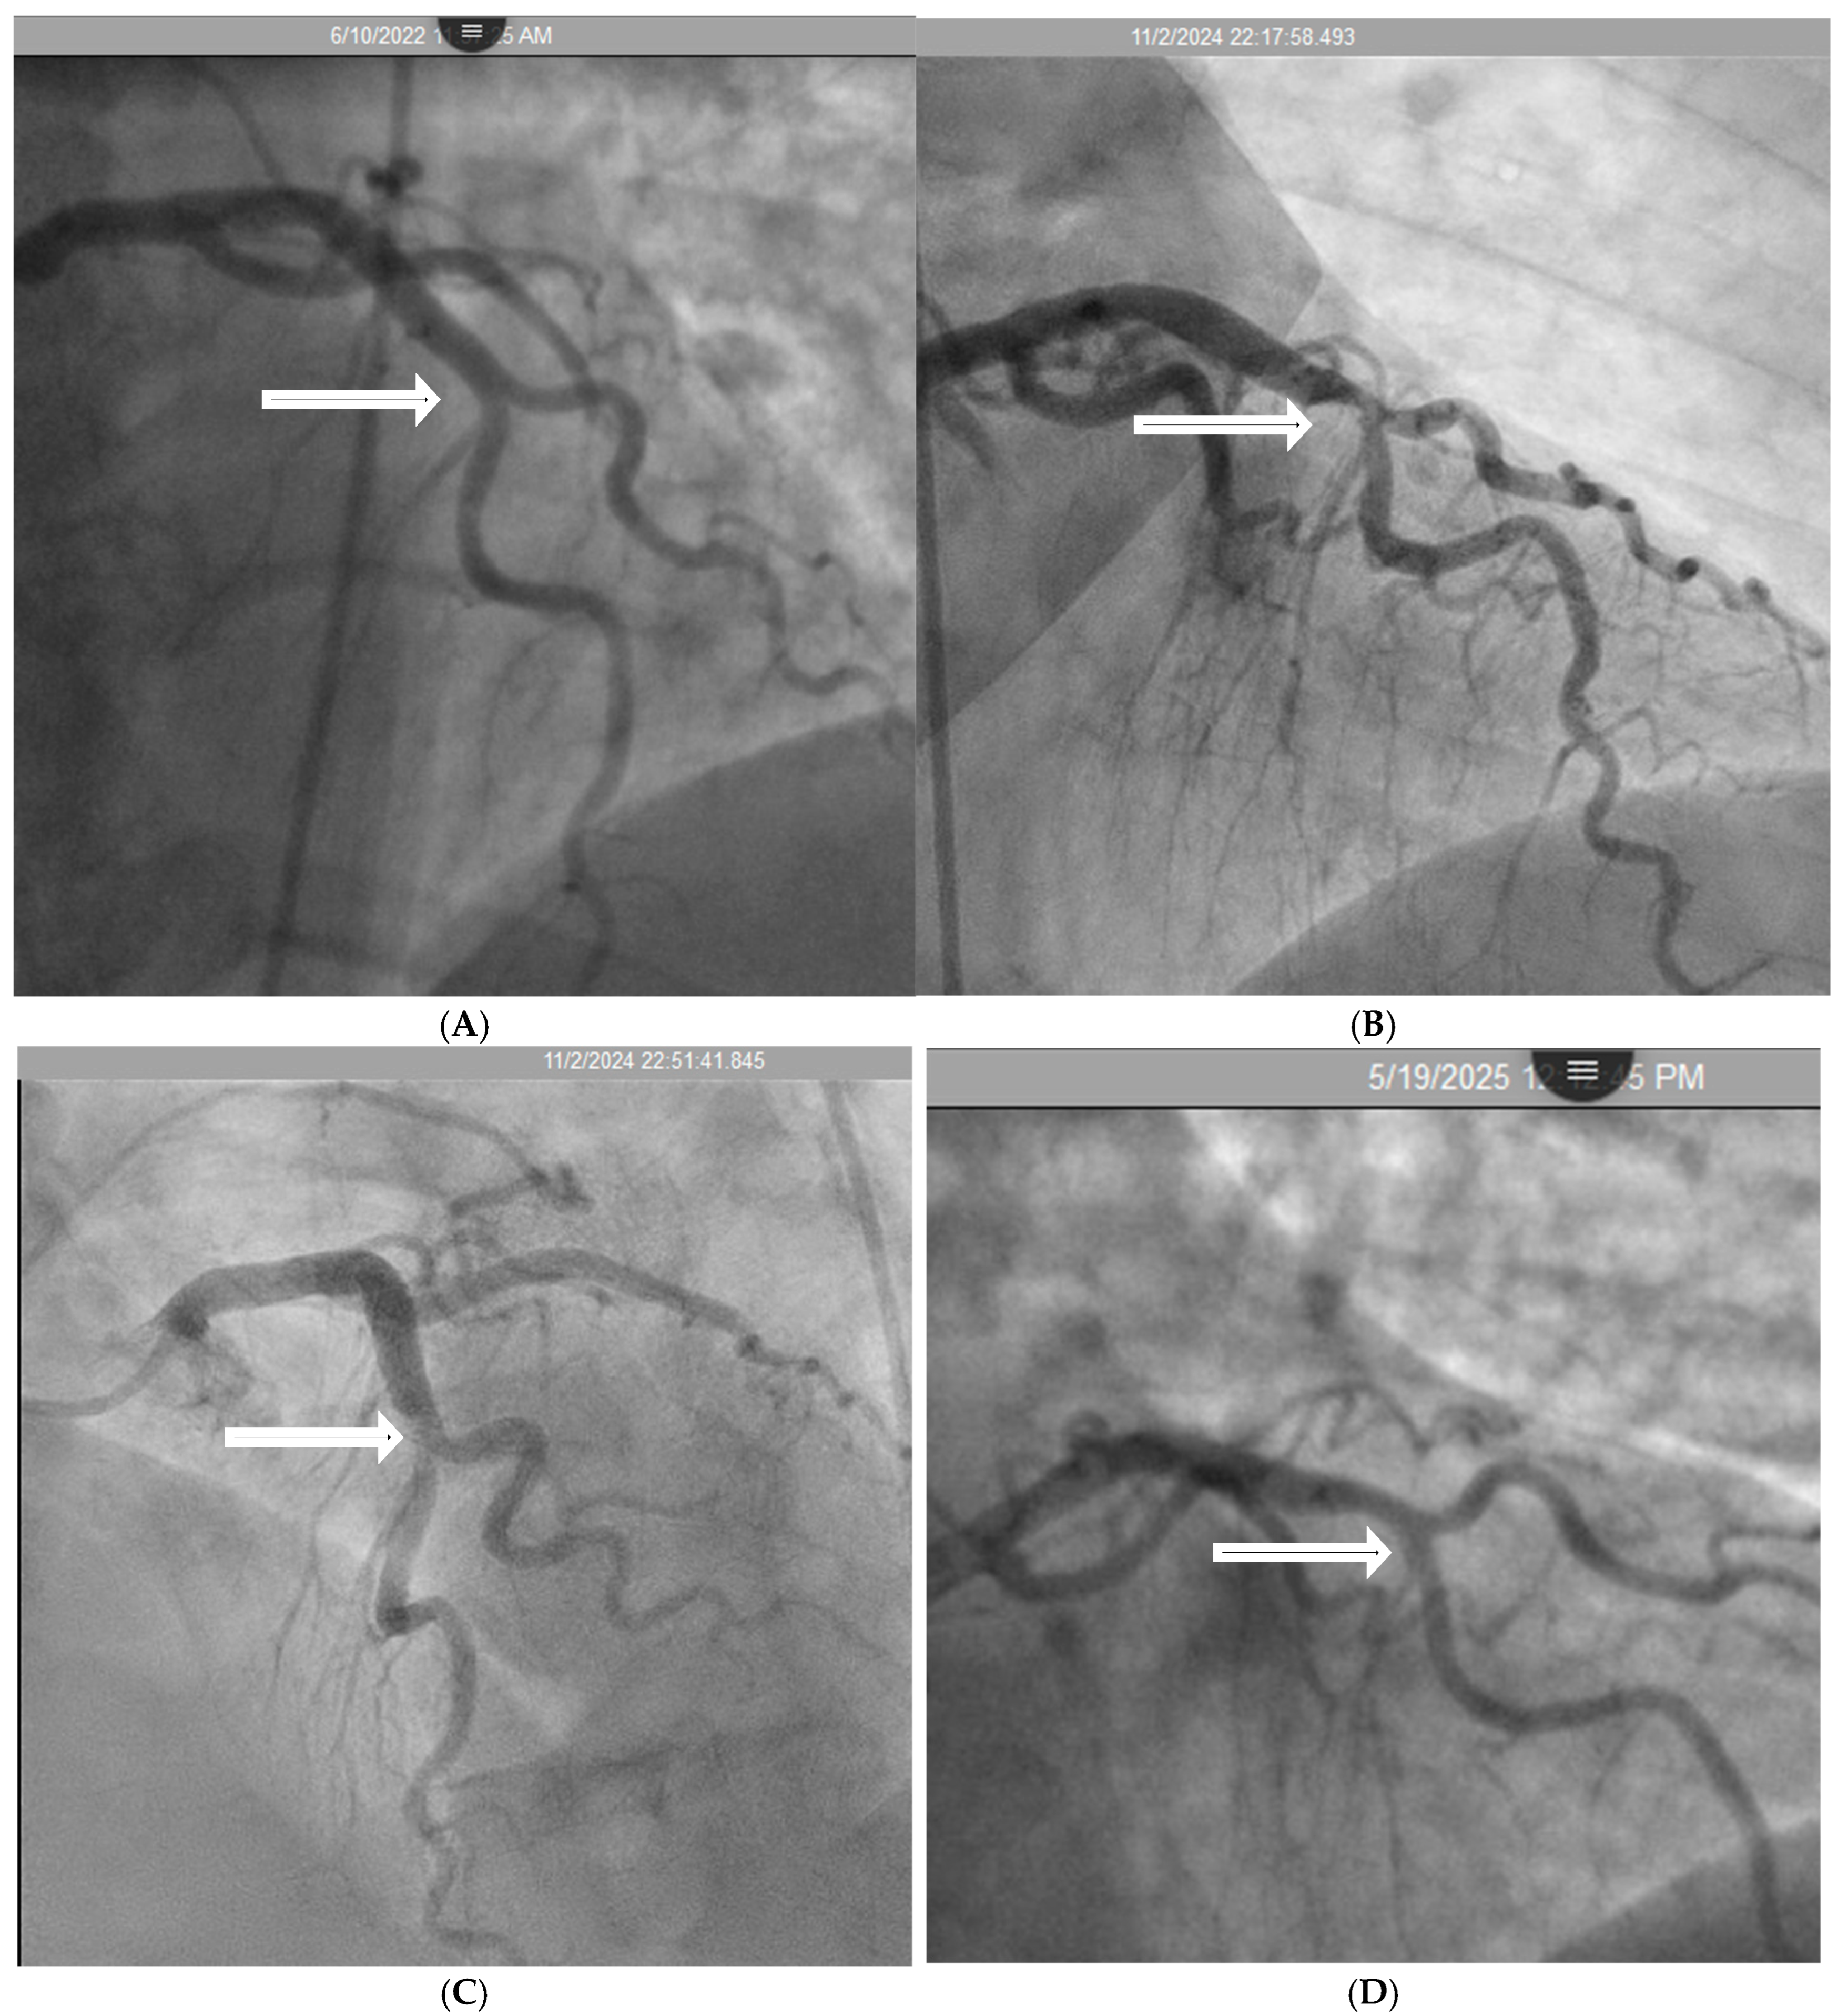

2.2. Mechanical Stress Due to Repetitive Bending at a Hinge Location

- Hinge Movement in Coronary Arteries:

- Coronary Angiographic Perspective:

- Coronary Dynamics Perspective:

- Acoustic Analysis of Coronary Angiographic Flow:

2.6. Codification of Lesions and Creation of a Coronary Acoustic Map